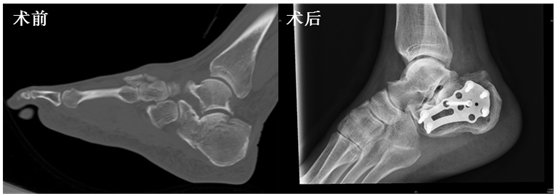

对于跟骨骨折,传统选用切开复位内固定手术,但该手术方式手术时间长,并发症多,切口皮肤坏死率高。本例患者为老年男性,因“摔伤后右足疼痛伴活动障碍3小时”入院,CT示右跟骨粉碎性骨折。手术过程中,张英泽院士采用其发明的克氏针闭合撬拨复位+微创接骨板固定,手术切口仅3厘米长,复位良好,手术时间短,实现了又快又好的手术目的。